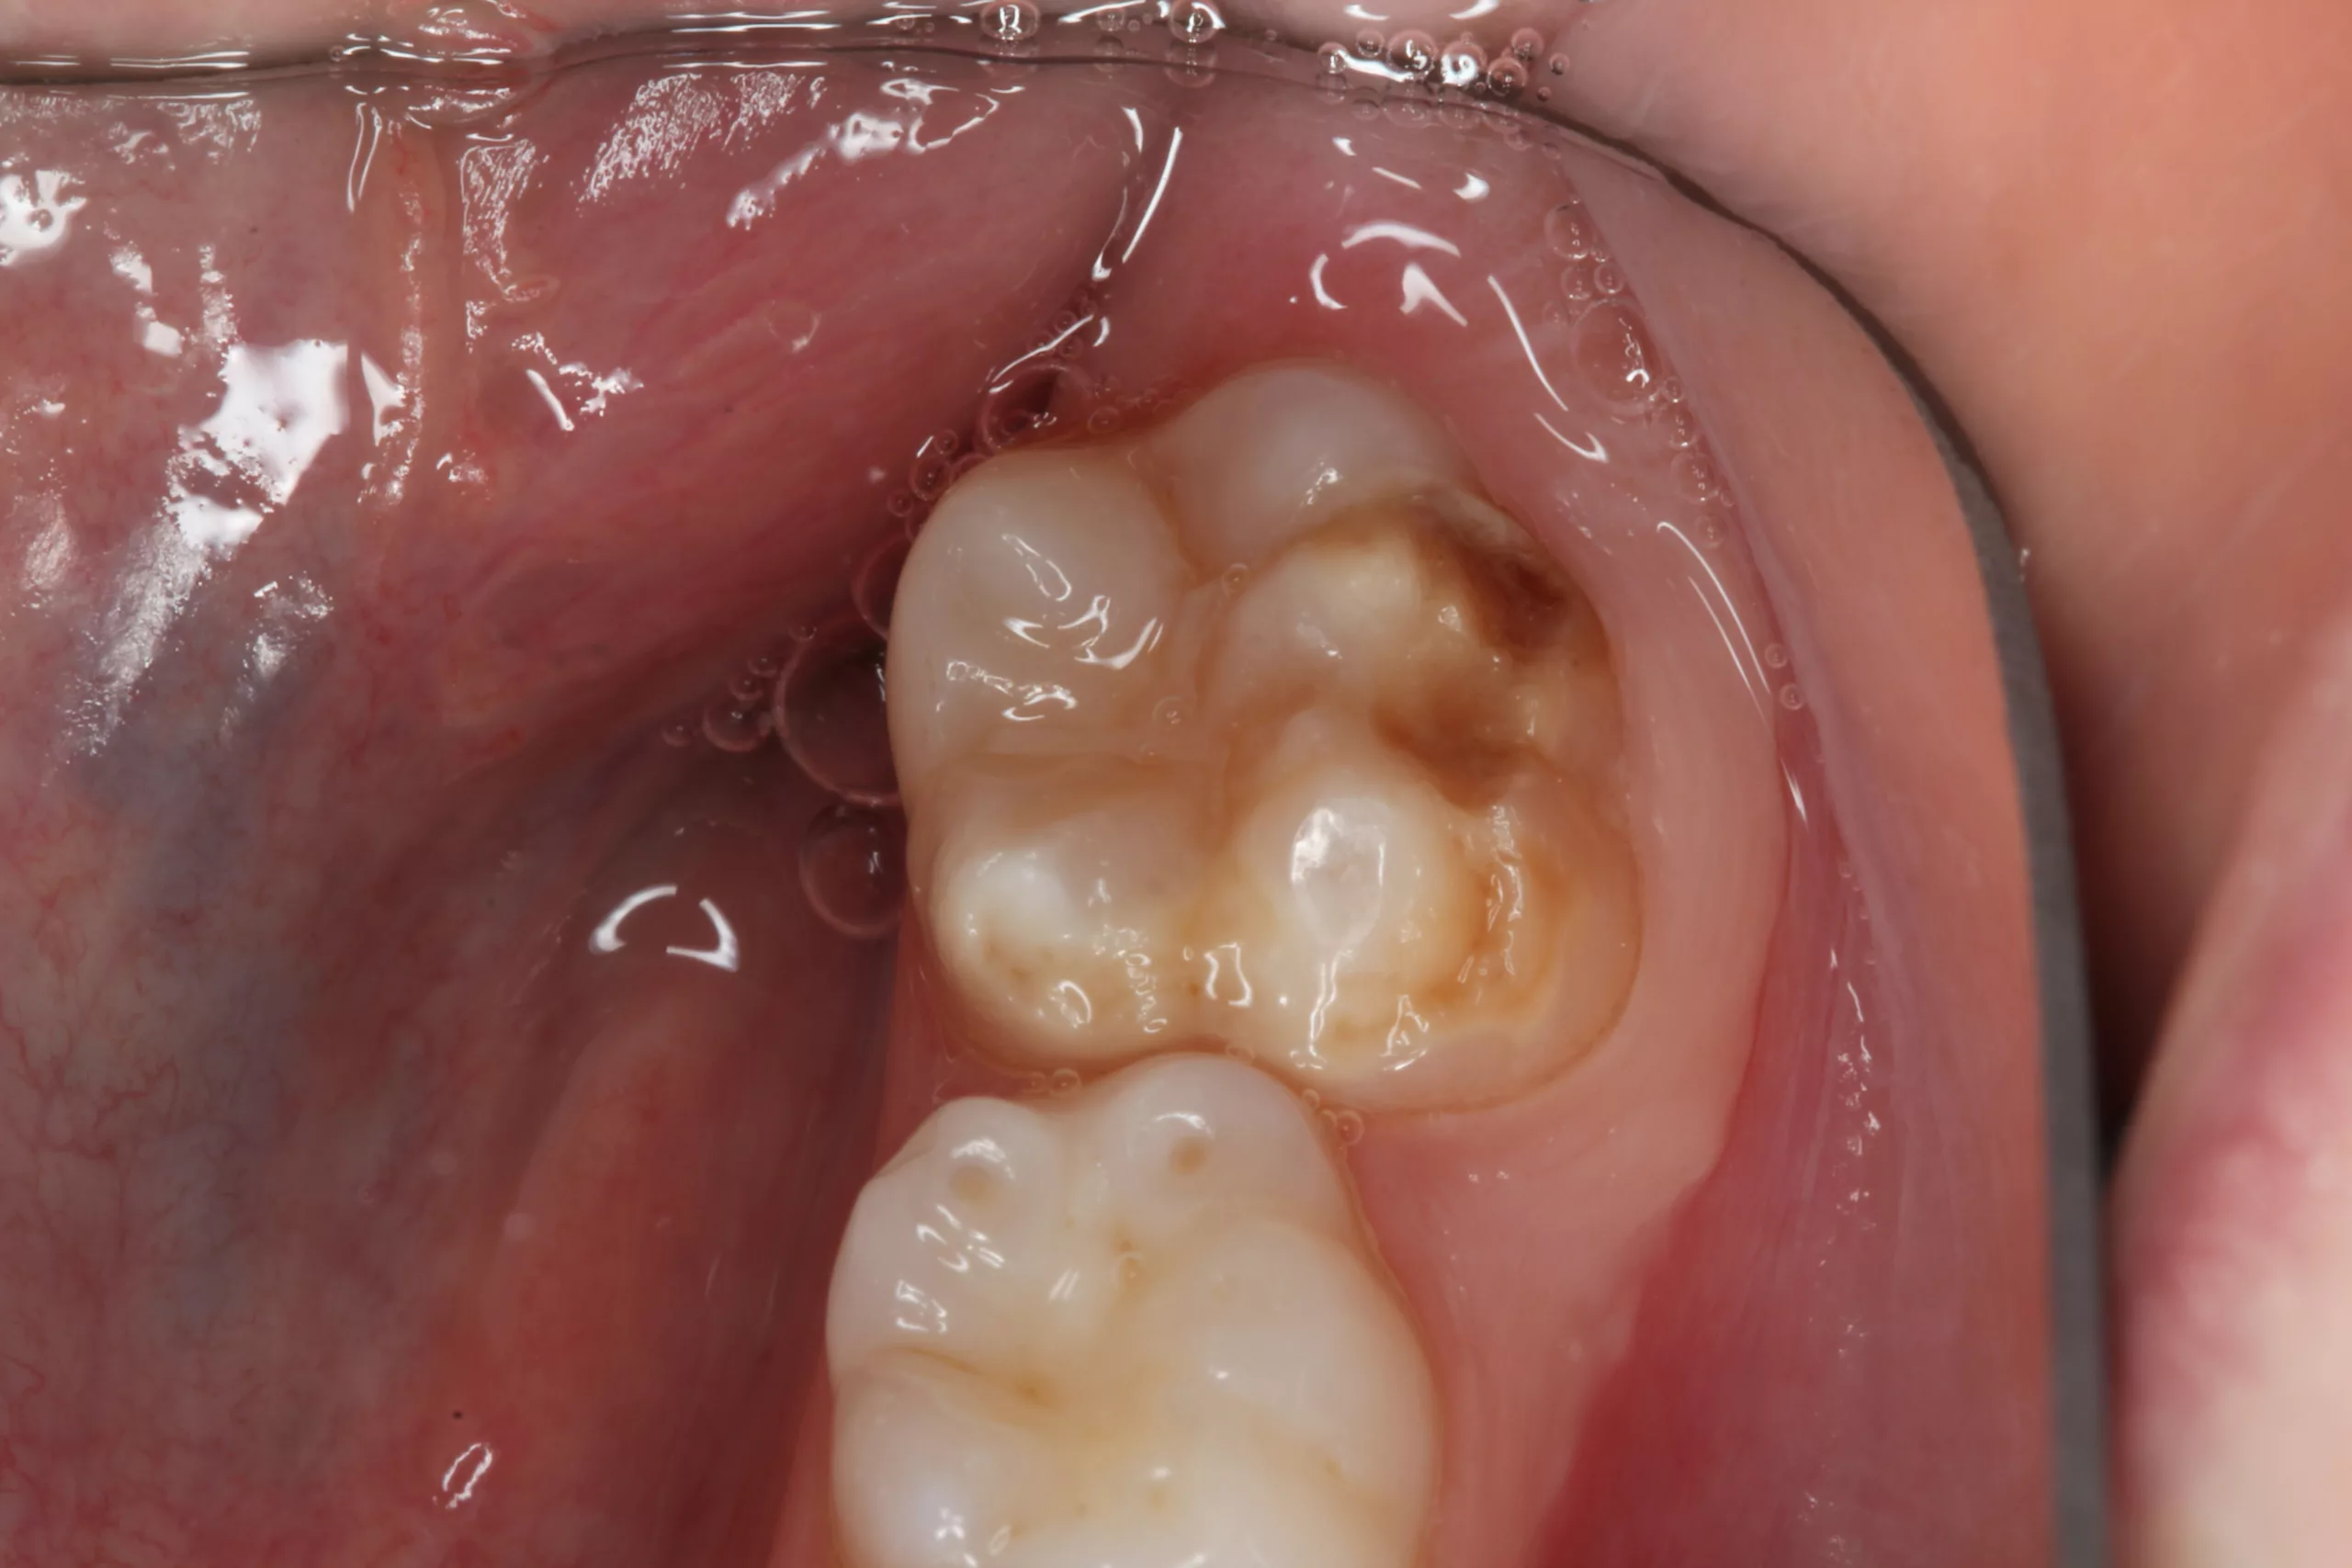

Es gibt Erkrankungen, die Ärzten und Wissenschaftlern Rätsel aufgeben. Zu diesen Krankheitsbildern zählen die sogenannten „Kreidezähne“, medizinisch „Molaren-Inzisiven-Hypomineralisation (MIH). Die Schmelzbildungsstörung tritt meist an den ersten bleibenden Backenzähnen auf, häufig auch an den bleibenden Frontzähnen. Untersuchungen zeigen: Auch Milchzähne können schon betroffen sein. Die Zähne haben weiße bis gelblich-braune Flecken – je größer und dunkler die verfärbten Stellen sind, desto stärker ist die Mineralisationsstörung.

„Bezogen auf die Mundgesundheit und die Lebensqualität der Kinder ist MIH mittlerweile ein größeres Problem als Karies in der Altersgruppe der 12-Jährigen“, beschreibt Prof. Dr. Dr. Norbert Krämer, Direktor der Poliklinik für Kinderzahnheilkunde, Justus-Liebig-Universität Gießen, die derzeitige Situation. „Wenn bereits Milchzähne von der Erkrankung betroffen sind, ist die Wahrscheinlichkeit, dass auch die bleibenden Zähne MIH haben, um rund 11 Prozent erhöht“, erklärt der Experte.